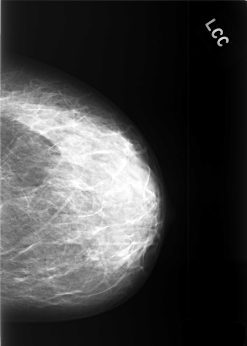

C_0421_1.LEFT_CC

LEFT_MLO LINES 5560 PIXELS_PER_LINE 3936 BITS_PER_PIXEL 12 RESOLUTION 50 NON_OVERLAY